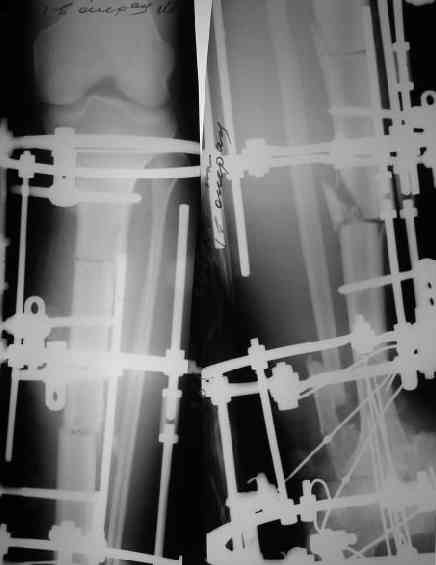

Билокально - все в два раза быстрее. Хотя это особенно сказывается в период фиксации, ждать перестройки 4 см регенерата надо раза в 3 дольше, чем 2 см. И если после дистракции все равно заштифтовать, то при монолокальном это было бы всего недели на 3 позже.

Нижняя остеотомия получилась грубовато. От этого регенерат там будет, наверно, похуже. И если бы он был только один, ждать перестройки пришлось бы даже боюсь предположить сколько.

После удостоворения, что остеотомия сделана по предварительному плану, теперь необходимо сделать контрольные снимки голеностопа. При первичной компрессии расширенная внизу вилка голеностопа и плюс мягкие ткани создают мягкотканую "гармошку". В зависимости от размера конечности у некоторых больных возникают трудности ношения обычной обуви после артродеза.

Снимки в приложении.

Да, при удалении таранной кости происходит гофрирование тканей. В данном случае есть еще и дублирование концов малоберцовой кости, которое должно устраниться при дистракции.